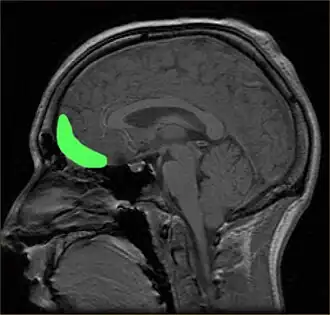

Although the precise neural mechanisms underlying disorders of impulse control are not fully known, the prefrontal cortex (PFC) is the brain region most ubiquitously implicated in impulsivity.[150] Damage to the prefrontal cortex has been associated with difficulties preparing to act, switching between response alternatives, and inhibiting inappropriate responses.[144] Recent research has uncovered additional regions of interest, as well as highlighted particular subregions of the PFC, that can be tied to performance in specific behavioral tasks.

The precise genetic and environmental factors contributing to ADHD are relatively unknown, but endophenotypes offer a potential middle ground between genes and symptoms.[41] ADHD is commonly linked to "core" deficits involving "executive function," "delay aversion," or "activation/arousal" theories that attempt to explain ADHD through its symptomology.[41] Endophenotypes, on the other hand, purport to identify potential behavioral markers that correlate with specific genetic etiology. There is some evidence to support deficits in response inhibition as one such marker. Problems inhibiting prepotent responses are linked with deficits in pre-frontal cortex (PFC) functioning, which is a common dysfunction associated with ADHD and other impulse-control disorders.[42][43]